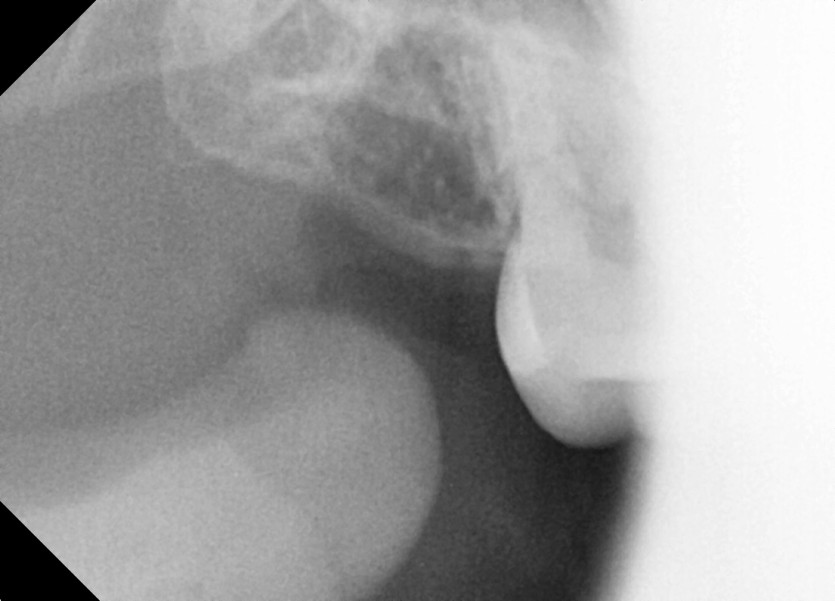

#18,28,38,48 사랑니 발치

구강 외과 전문의가 당일 발치했습니다.